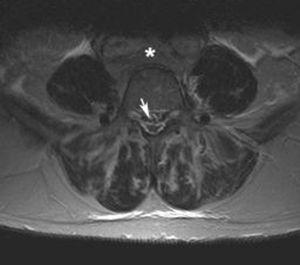

Fig. 1. Resonancia magnética ponderada en T1 (A) sagital línea media, (B) parasagital y (C) axial. (A) Aumento de la grasa epidural que comprime el saco tecal debido a lipomatosis (flecha); (B) imágenes hipointensas puntiformes en el espacio epidural anterior que corresponden a estructuras vasculares dilatadas del plexo lumbosacro (flechas); (C) masa retroperitoneal que engloba grandes vasos (asterisco). Se objetiva la presencia de lipomatosis (flecha blanca) y las estructuras vasculares dilatadas (punta de flecha blanca).